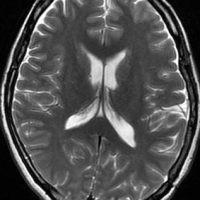

左は,造影剤を使ったガドリニウム増強MRIです。腫瘍が白く丸く見えます。右はフレア画像で,腫瘍の周囲の脳浮腫(脳のはれ)です。左前頭葉が,かなり強くはれています。この腫瘍は小さいのですが,脳のはれが強すぎるので手術摘出したほうがいいです。浮腫が悪化すると,てんかん発作や認知機能低下がでる可能性があります。

脳浮腫(脳のはれ)

- 髄膜腫が発見されると「まわりの脳が腫れている」と説明されることがあります

- これを腫瘍周辺脳浮腫 peritumoral brain edema といいます

- 髄膜腫の20-30%くらいでみられます

- 脳浮腫が強いと,はれている部分の脳の機能が落ちます

- 認知症,感覚障害,運動麻痺,失語症,てんかん発作などの症状が出やすくなります

- 髄膜腫が全部とれると,この脳の腫れも消えます

- 腫瘍血管が増える時にVEGFが産生されるために,脳の細血管の透過性が亢進して,血液の中の血漿成分が脳組織の中に漏れ出ることが原因です